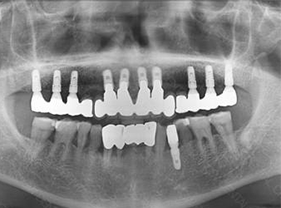

治療です。 前後写真

入れ歯の不快感を解消し、全顎インプラントを完成させます。

自然な機能と審美性の両方を満たす結果です。